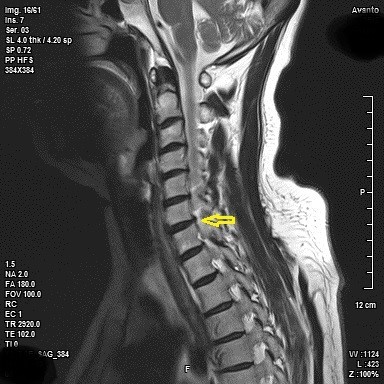

오늘은 목 건강을 위협하는 질환, **목디스크(경추 추간판 탈출증)**의 증상에 대해 이야기하려 합니다. 목디스크는 목뼈 사이에 있는 디스크가 제자리를 벗어나 신경을 압박하면서 발생하는 질환입니다.

- 하지 마비 및 보행 장애

- 설명: 목디스크가 심하게 진행되어 척수를 압박하면 하체까지 증상이 나타날 수 있습니다. 다리에 힘이 빠지고, 보행이 불안정해지며, 심한 경우 마비 증상이 나타나기도 합니다. 이는 즉시 치료가 필요한 심각한 합병증입니다.